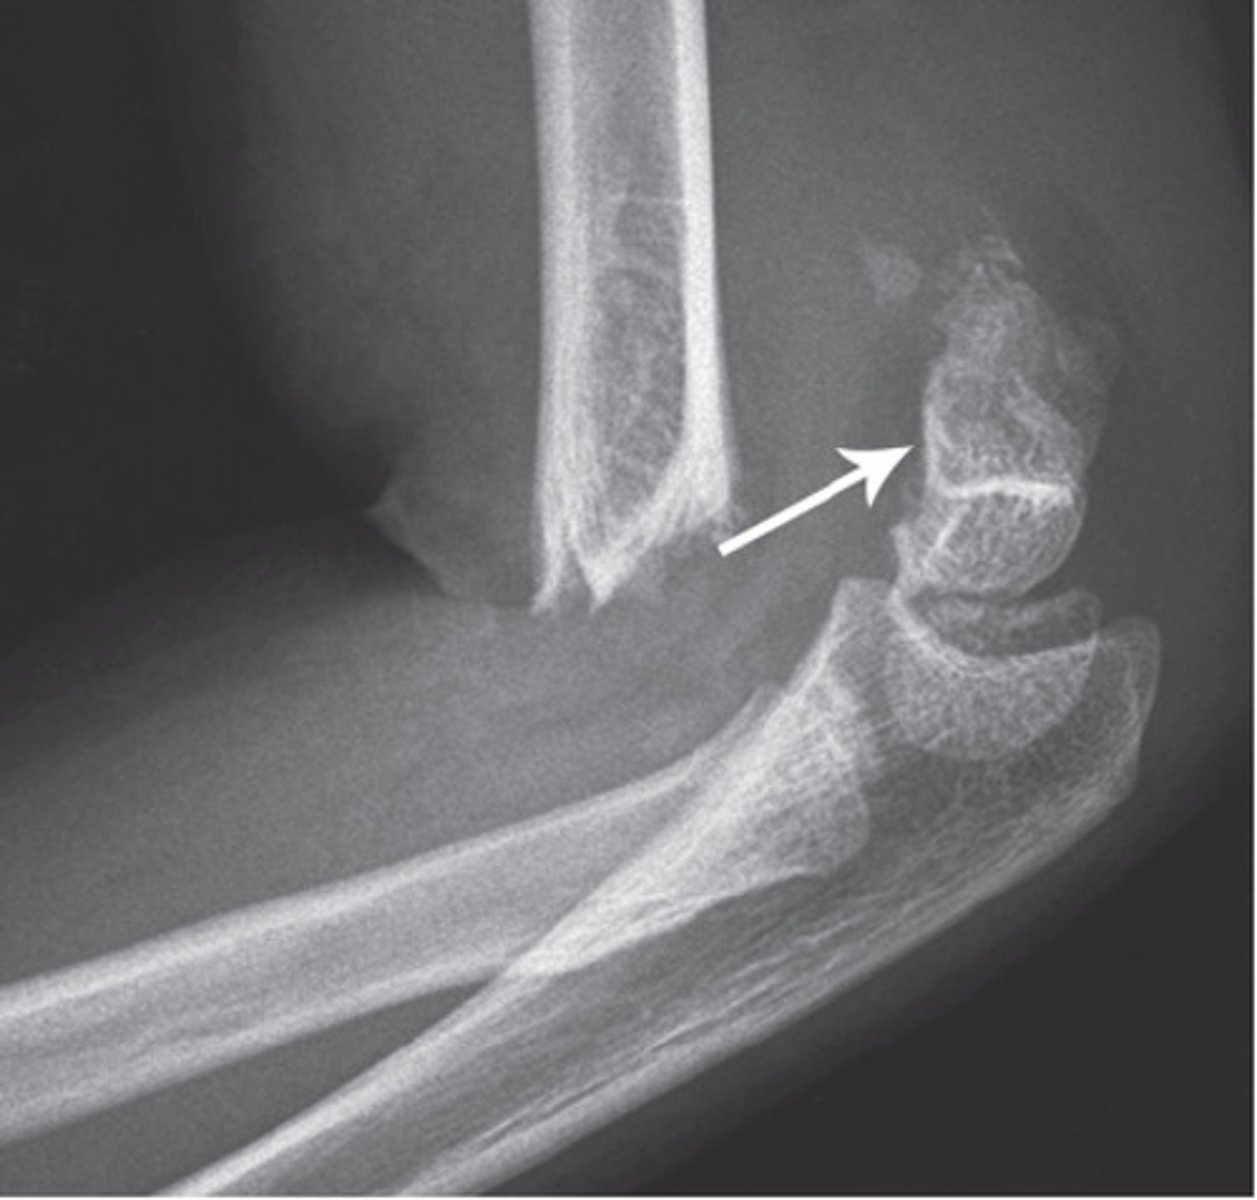

supracondylar fracture

distal humeral fracture

common in kids

typically AIN (branch of median nerve) and brachial artery involvement

complications: volkmanns ischemic contracture, gun stock deformity (reduced carrying angle), high incidence of malunion

requires ORIF